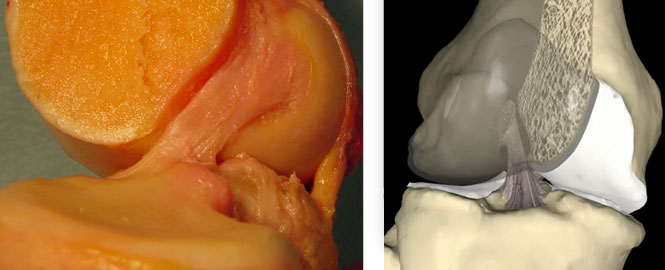

Lesão do Ligamento Cruzado Anterior (LCA) do Joelho

O ligamento cruzado anterior (LCA) é o principal estabilizador do joelho, impedindo o deslocamento anterior da tíbia em relação ao fêmur. Pacientes com lesão do LCA frequentemente relatam um episódio de entorse ou trauma no joelho, seguido de inchaço, dor e, posteriormente, sensação de falseio.

A instabilidade causada por essa lesão pode levar a lesões degenerativas da cartilagem articular a partir de 6 meses. Após 5 anos de lesão, 50% dos pacientes desenvolvem artrose no joelho, e após 10 anos, 75% apresentam esse quadro.

Em 50% dos casos, pacientes com lesão do LCA também possuem lesões meniscais associadas, sendo mandatório investigar essas ocorrências. O exame clínico, com testes como Lachmann e Pivot Shift, possui alta acurácia no diagnóstico.

Tratamento

Atualmente, a indicação de tratamento para indivíduos fisicamente ativos que apresentam instabilidade anterior do joelho é a reconstrução ligamentar com enxertos. Os enxertos mais utilizados são os tendões da pata de ganso (semitendinoso e grácil) e o tendão patelar.

A reconstrução do LCA com tendões flexores (grácil e semitendinoso) é uma técnica que apresenta menor morbidade, pós-operatório menos doloroso e melhor estética, por não envolver um acesso anterior no joelho. Funcionalmente, os enxertos mencionados são equivalentes e têm respaldo na literatura.

Os pacientes são orientados a mobilizar e apoiar precocemente o membro inferior acometido, com acompanhamento de fisioterapeuta e educador físico. Geralmente, são liberados para retornar às atividades físicas de contato após 6 meses.